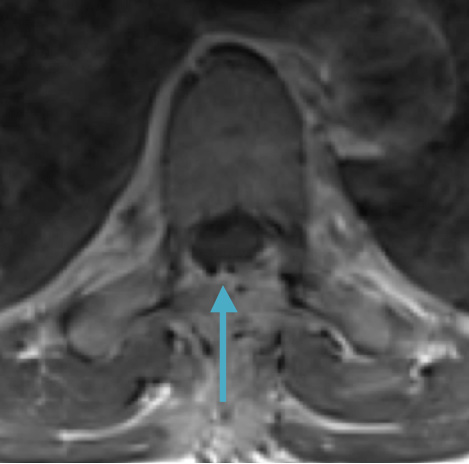

Preoperative MRI T2 demonstrating obstruction of CSF around the cord (blue arrow), resulting from the tumor (red arrow)